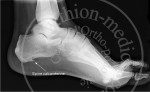

Semelles EPITAL pour épine calcanéenne

Le relief anatomique plantaire, répartit le poids du corps, tandis que la zone d’évidement de l’épine calcanéenne, décharge de toute pression et soulage la douleur.